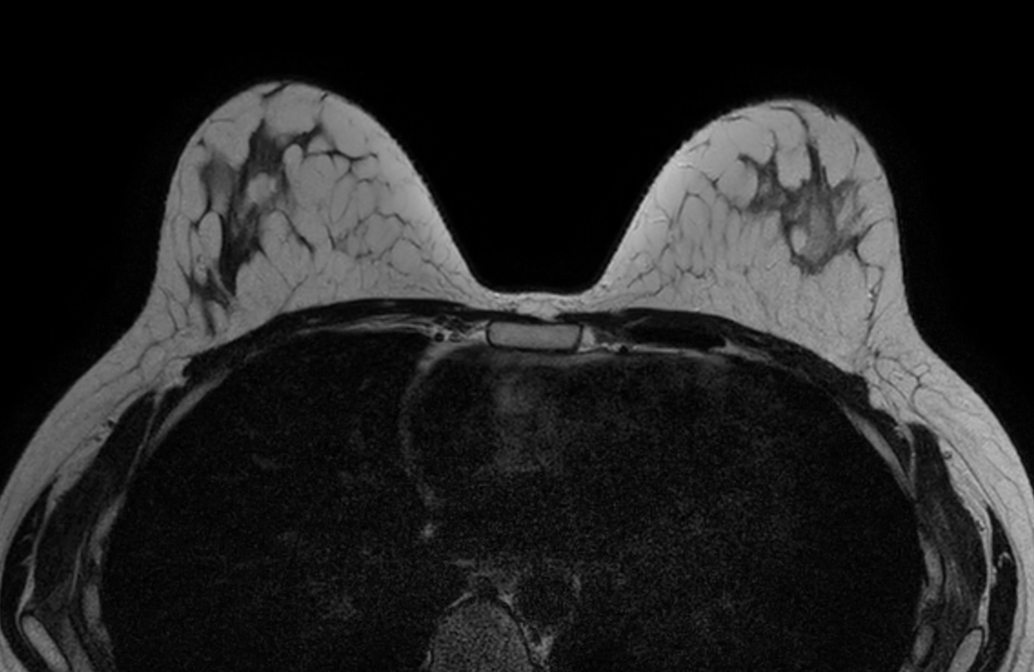

Axial mDIXON XD FFE (In Phase) - Dyn 1

Axial mDIXON XD FFE (Water only) - Dyn 1